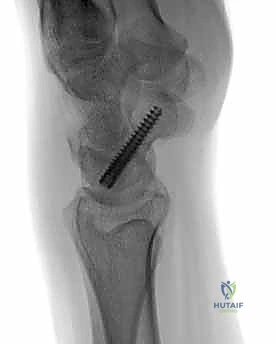

تقنية "التثبيت عن طريق الجلد" (Percutaneous Fixation) هي إجراء جراحي طفيف التوغل (Minimally Invasive). بدلاً من فتح الرسغ، يقوم الجراح بإجراء ثقب صغير جداً في الجلد (لا يتجاوز 3-5 مليمترات). من خلال هذا الثقب، وباستخدام جهاز الأشعة السينية المباشر في غرفة العمليات (C-arm Fluoroscopy)، يتم إدخال سلك توجيهي دقيق، ثم يتم إدخال مسمار خاص يسمى "مسمار ضغط بدون رأس" (Headless Compression Screw) مثل مسمار هيربرت (Herbert Screw).

هذا المسمار العبقري يتم دفنه بالكامل داخل العظم (تحت سطح الغضروف حتى لا يحتك بالمفاصل الأخرى)، ويتميز بوجود أسنان لولبية (Threads) في طرفيه بمسافات مختلفة. هذا التصميم يجعله يسحب طرفي الكسر ويضغطهما معاً بقوة هائلة (Compression)، مما يحفز التئام العظم بسرعة فائقة ويمنع أي حركة بين طرفي الكسر.

2. المدخل الظهري (Dorsal Approach): من ظهر اليد. يُعتبر الأفضل لكسور القطب القريب، حيث يوفر مساراً أسهل للوصول إلى هذا الجزء العميق بمحاذاة المحور الميكانيكي للعظم.